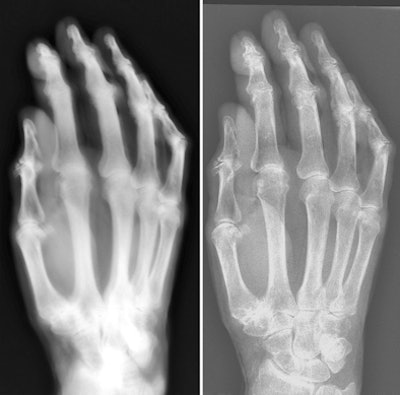

![]() |

| Images of the hand specimen of an 86-year-old woman obtained with vintage x-ray machine (left) and a modern x-ray system (right). The exposure time with the 1896 system was 21 minutes. |

Although the study revealed the primitive nature of early work in radiology, the researchers said that ultimately they were impressed with the image quality of the device.

"Images of the hand specimen obtained with the antiquated system were severely blurred but were still awe inspiring, considering the simplicity of the system," they concluded.